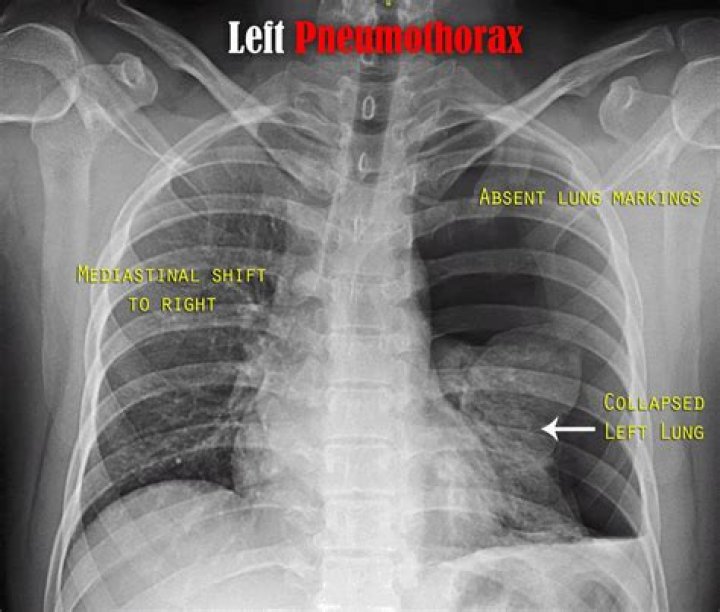

Pneumothorax, sometimes abbreviated to PTX, (plural: pneumothoraces) refers to the presence of gas (often air) in the pleural space.

Pneumothorax is when air collects in between the parietal and viscera pleurae resulting in lung collapse. It can happen secondary to trauma (traumatic pneumothorax). When mediastinal shifts accompany it, it is called a tension pneumothorax. This is a life-threatening emergency that needs urgent management.

Tension pneumothorax is accumulation of air in the pleural space under pressure, compressing the lungs and decreasing venous return to the heart.

A tension pneumothorax is a life-threatening condition that develops when air is trapped in the pleural cavity under positive pressure, displacing mediastinal structures and compromising cardiopulmonary function. Prompt recognition of this condition is life saving, both outside the hospital and in a modern ICU.